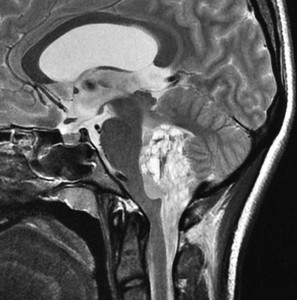

第4脳室上衣腫(良性と言える思春期例:EPN-PFB)

青年に発生したものです。かなり分化度の高い延髄背側 ovex 発生の上衣腫です。境界が明瞭なのですが,実際に側方(延髄小脳脚槽)で椎骨動脈や後下小脳動脈,下位脳神経に癒着しているので剥離は必ずしも容易ではありません。この例では幸い全摘出できました。

手術ビデオは下をクリックするとYouTubeでみえます

摘出した標本のHE染色です。左側ではperivascular pseudorosette(血管周囲の無核野)がみられ,右側ではependymal tube (ependymal canal) が認められます。

左がGFAP染色、右がMIB-1(Ki-67)染色です。 GFAPは腫瘍血管の周囲の無核野に強陽性です。MIB-1 labelling index が1%以下であり,この上衣腫の増殖能が極めて低いことを示しています。このような高分化型で増殖能の低い上衣腫は脊髄髄内には多いのですが,脳では珍しいものです。ovex中心上衣腫にみられます。